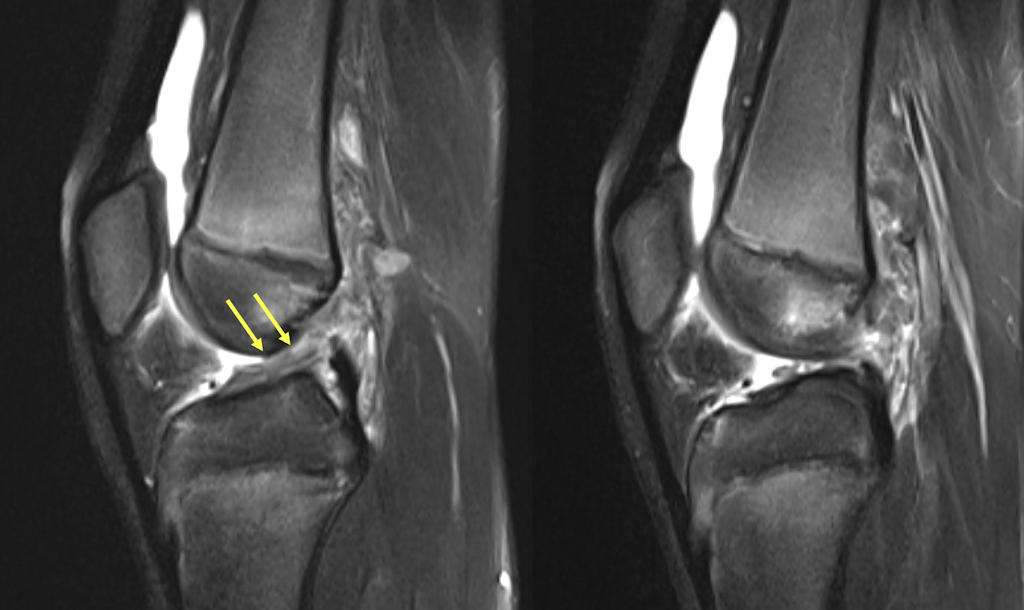

Orta yaştaki menisküs kök yırtıklarında tedavi yaklaşımı değişti

Menisküs yırtıkları, dizin en sık görülen sorunlarından birisidir. Genç hastalarda, bir şiddetli bir dönme hareketi veya darbe sonrası oluşan menisküs yırtıkları ile; ileri yaşta, basit bir çömelme veya halıya takılma sonrası oluşan yırtıkların farklı özellikleri vardır. Genç hastalarda oluşan yırtıklar, sağlam menisküste şiddetli bir zorlanma sonrasında ortaya çıkar ve genellikle cerrahi tedavi gerektirir.